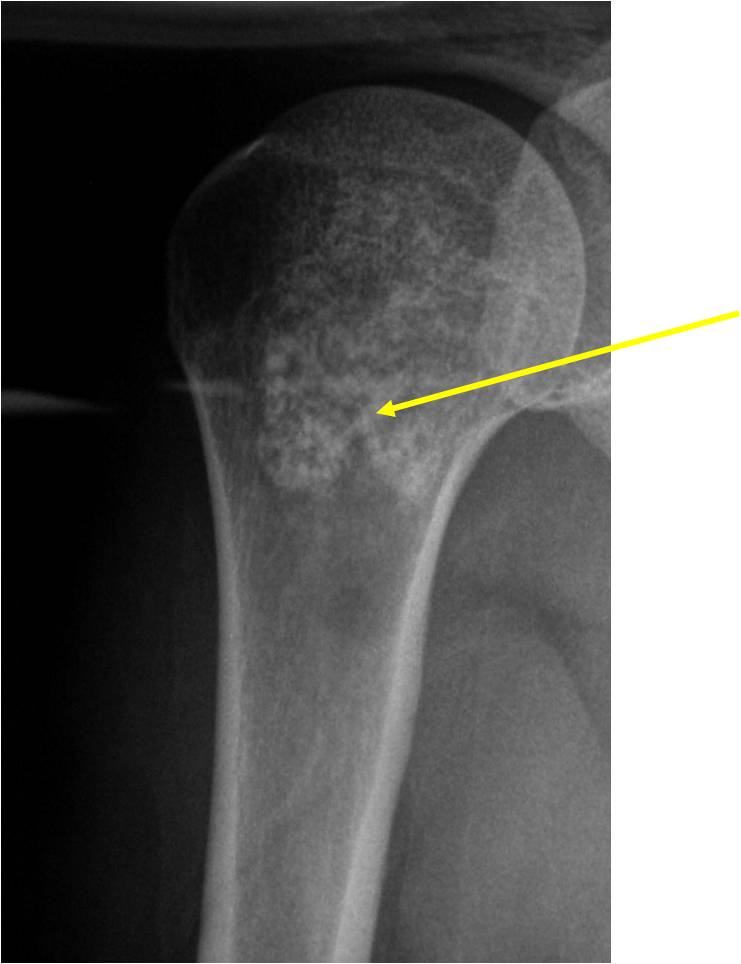

- Localized, radiolucent defect usually with punctate calcifications

- Calcifications are typical but not always present

- Matrix may demonstrate various degrees of calcification

- Calcifications are stippled, punctate, popcorn like calcifications and “Ring and Arc” calcifications

- Cartilage tumors grow in a lobular manner. The perimeters of the lobules undergo

- enchondral ossification that may calcify. If the entire perimeter of the lobule calcifies it appears

- radiographically as a “Ring”. If a portion of the perimeter of a lobule calcifies it forms an “Arc” on

- an X-ray.

- May be located centrally or eccentrically

- Most commonly found in metaphysis

Ring and Arc Calcifications, Minimal Endosteal Scalloping, Cortex Intact, No Soft Tissue Component, No Periosteal Reaction

Minimal Endosteal Scalloping is Acceptable

Metaphyseal Tumor, Heavy Calcifications, Ring and Arc Pattern of Calcifications, Minimal Endosteal Scalloping, No Cortical Destruction, No Periosteal Reaction, No Cortical Destruction, No Soft Tissue Component

Metaphyseal Tumor, Heavy Calcifications, Ring and Arc Pattern of Calcifications, Minimal Endosteal Scalloping, No Cortical Destruction, No Periosteal Reaction, No Soft Tissue Component